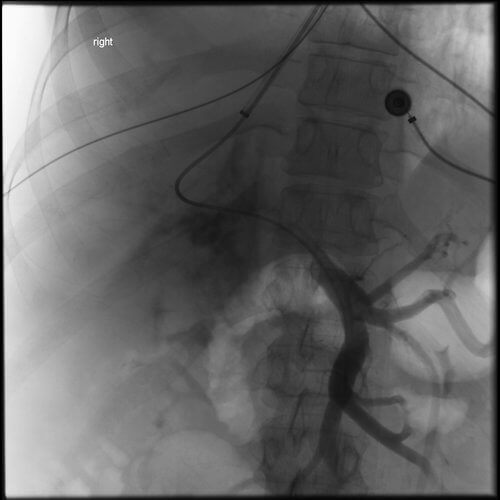

Comment: Attempts were made to place a TIPS in this patient from a hepatic vein approach. However, no recognizable hepatic veins were evident and no collaterals could be accessed percutaneously. As a result, we placed an 18g Chiba needle using a transhepatic approach from the midaxillary line; the needle was directed towards the RA-IVC junction. At the same time, the right internal jugular vein was accessed and a snare was positioned in the upper IVC. The needle was directed towards and passed through the snare. A guidewire was then advanced through the needle and that wire was pulled into the IJ sheath by the snare. A 5F sheath was then advanced from the liver into the IVC and a second wire was placed through the sheath and captured (in order to have a safety wire). At this point, the intrahepatic tract was dilated and a 10F sheath was advanced from the neck into this new tract through the liver. A CO2 venogram was then performed, followed by creation of a TIPS through this tract, extending from the right portal vein into IVC. Note that once the first stent was in place, it was short of the IVC so additional stents had to be placed. In addition, thrombus was noted at the origin of the right portal vein with preferential flow into the left portal vein. Mechanical thrombectomy had to be performed to insure portal vein and TIPS patency. At the conclusion of the procedure, the portosystemic pressure gradient decreased from 39 mm Hg to 10 mm Hg.